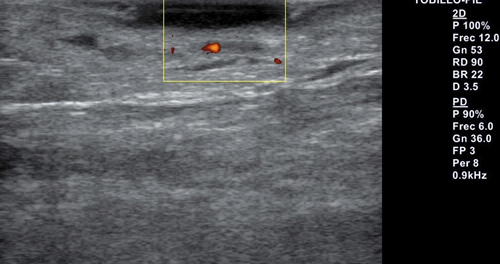

Se realiza exploración ecográfica vascular empleando para ello un equipo Alpinion E-cube 7 con una sonda lineal de 3-12 mHz, con una frecuencia de 12 mHz en la que destaca insuficiencia venosa y onda trifásica en arterias pedia y tibial posterior. Se realiza ecografía transulcerosa (Figura 2) mostrando área anecoica con punteado hiperecoico en su interior y con leve refuerzo acústico posterior, que afecta a la totalidad de la epidermis y penetra en dermis. Lesión bien delimitada, con ausencia de doppler en el interior de esta (Figura 3). Presenta una extensión ecográfica de 14 x 3.4 mm.

Figura 3. Ecografía transulcerosa con ausencia de doppler en el interior de la lesión.